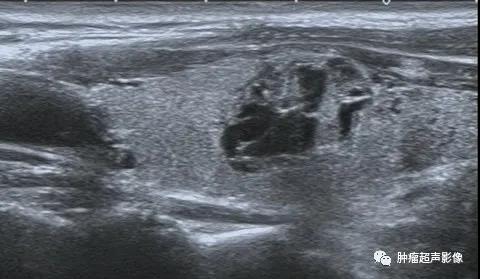

上图:甲状腺结节呈低回声,边缘不光整,纵横比大于1,内见点状强回声,可分到5类,内部无血流,

回顾以前检查可发现同一位置有一囊实性结节(下图),从而确诊皱缩结节,避免穿刺及手术。